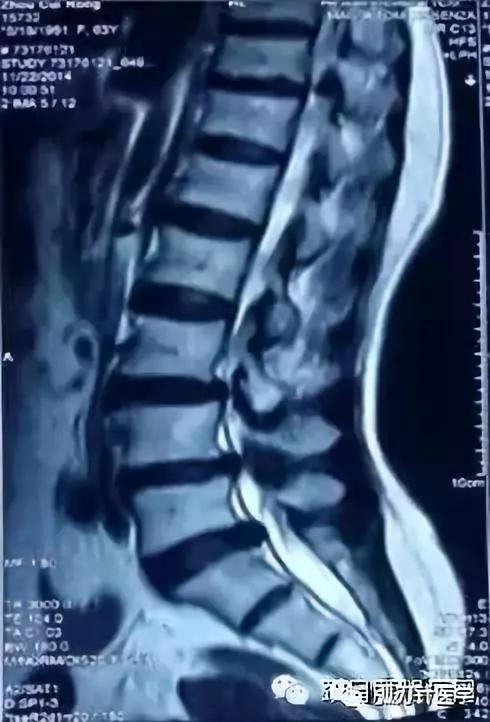

腰椎管狭窄的影像学改变

CT:诊断符合率96% —100%,正常CT椎管形态为三角形或球形,狭窄的可显示为三叶草、牛角、猫耳形。Korkard测量侧窝神经根管矢径大于5mm 为正常,4 mm 为临界.小于 3mm 为狭窄。椎管与椎体矢状径比值在椎弓板上切迹层面小于0.45 ,在椎间盘层面小于0.35可以确诊,硬膜囊与椎管矢状径比值如低于0.6 以下可以确认。近年来又有CT计算机图形计算椎管横截面积CSAC自L1-S1,逐渐加大,硬膜囊横截面积(CSADS)自L1-S1,逐渐减小,来评估椎管狭窄。 MRI :它不能提供精确的定位与清晰的图像,诊断符合率占 82%一 91%,但在鉴别诊断方面可显示椎管。